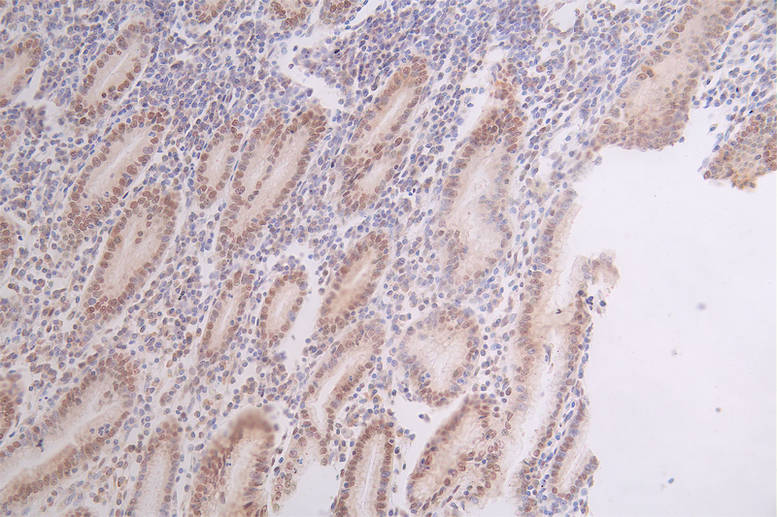

IHC image of CSB-RA796958A0HU diluted at 1:50 and staining in paraffin-embedded human breast cancer performed on a Leica BondTM system. After dewaxing and hydration, antigen retrieval was mediated by high pressure in a citrate buffer (pH 6.0). Section was blocked with 10% normal goat serum 30min at RT. Then primary antibody (1% BSA) was incubated at 4°C overnight. The primary is detected by a Goat anti-rabbit polymer IgG labeled by HRP and visualized using 0.67% DAB.